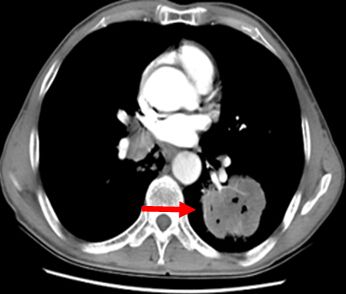

患者任某,女,60岁,患者因刺激性咳嗽3个月,右上腹部疼痛2个月于2014年4月11日就诊。入院后行肺增强CT、全腹增强CT;:左肺下叶支气管开口周围见类圆形肿块影,大小约为4.75×4.54cm,肿块包绕左肺下静脉及左肺下动脉干,肿块不均匀强化,左肺下叶支气管开口截断,左肺下叶内前基底段肺组织实变。左肺门见肿大淋巴结与肺门肿块融合。肝脏大小及形态未见确切异常,肝实质内弥漫性分布低密度肿块影,肿块融合成团,约占据整个肝脏,增强检查环形强化,选择病灶2.81×2.68cm,腹腔内见多个肿大淋巴结,融合成团,包绕邻近组织,较大约为3.21×2.57cm,左侧肾上腺见类圆形肿块影,大小约为2.49×1.99cm,增强检查略强化。明确诊断为:左肺下叶小细胞肺癌(T2aN1M1b)Ⅳ期,广泛期、左肺门淋巴结转移、 多发肝转移、腹腔淋巴结转移。符合我院正在进行的Ipilimumab联合EP治疗广泛期小细胞肺癌的III期临床研究,给予入组。于2014年5月1日开始给予EP方案化疗(VP-16,100mg/m2,157mg,d1-3;DDP,75mg/m2,118mg,d1),共给予化疗4周期,第3周期开始给予加用Ipilimumab单抗(10mg/kg),现患者已应用2周期,无明显严重不良反应发生。2周期后疗效判定:靶病灶1、左肺内病灶消失,2、左肾上腺转移病灶11.6×9.5=110.2,3、肝转移病灶11.3×9.1=102.83。靶病灶乘积之和213.03,疗效判定PR,非靶病灶:1、肝内其他转移病灶,存在,2、腹腔其他转移淋巴结,存在,疗效判定SD,总体疗效判定PR。现患者仍在继续用药中。

2014年4月29日治疗前